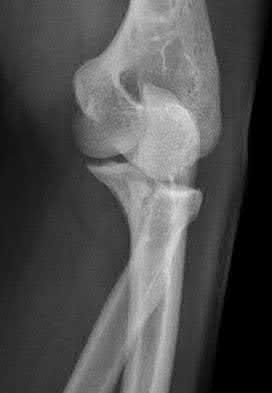

1012) A 54-year-old woman sustains the injury seen in Figures 71a and 71b. The injury involves her nondominant extremity. What should the patient be told regarding her expected outcome?

Corrent answer: 3

This is a Bado type 2 (posterior) Monteggia lesion, which is associated with higher rates of complications than other types of Monteggia lesions. The injury is associated with indirect high-energy trauma and less often pathologic causes. Of the four types of Monteggia lesions, the type 2 or posterior type is associated with the worst prognosis. These injuries are best treated surgically with dorsal plating of the ulna and reduction with fixation or arthroplasty of the radial head. The major complications seen with this injury pattern are nonunion and plate failure. Almost all patients have some loss of elbow range of motion. Satisfactory results based on functional scores for this injury are not universal. Neurologic injury and ulnohumeral instability are unusual with this type of injury. Full functional recovery is not expected with nonsurgical management.